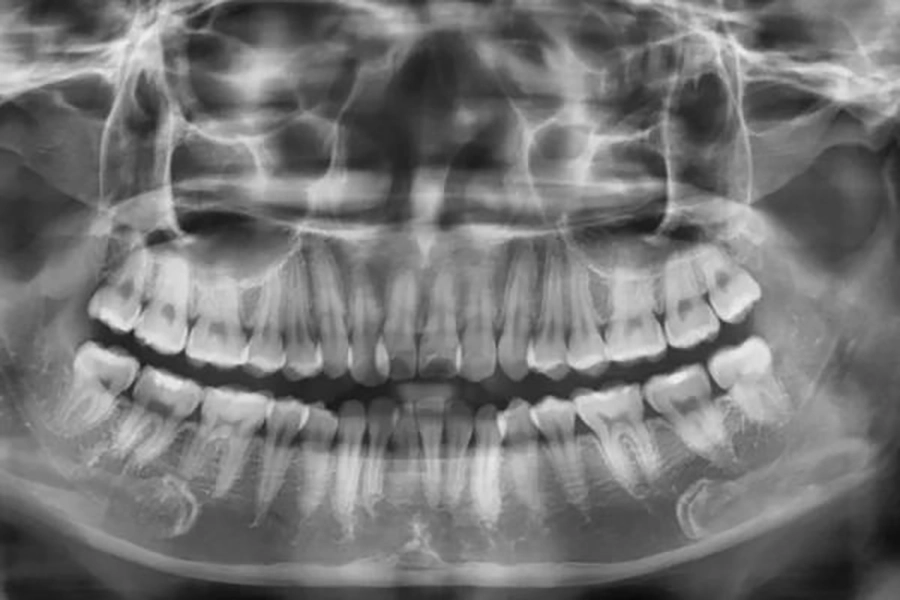

4.1 Thăm khám và chụp X-quang

Trước khi bắt đầu chỉnh nha, bác sĩ sẽ tiến hành thăm khám tổng quát để đánh giá tình trạng răng và khớp cắn của bệnh nhân. Đây là bước quan trọng để phát hiện những bệnh lý răng miệng tiềm ẩn như sâu răng, viêm nướu hoặc cao răng cần được xử lý trước khi niềng.

Song song đó, bệnh nhân sẽ được chụp X-quang hoặc CT Cone Beam 3D. Các hình ảnh này giúp bác sĩ quan sát rõ cấu trúc xương hàm, vị trí chân răng và mật độ xương, từ đó xác định chính xác mức độ sai lệch.

Kết quả thăm khám và hình ảnh chẩn đoán sẽ là cơ sở để xây dựng phác đồ điều trị phù hợp, đảm bảo hiệu quả tối ưu cho từng trường hợp.